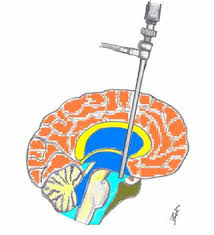

Şant implantasyonu. Hidrosefalide en sık uygulanan tedavi yöntemidir. Şant adı verilen bir drenaj sistemi cerrahi olarak yerleştirilir. Uzun, ince bir tüp şeklinde, fleksibl valv yapısına sahip olan bu sistem; sıvının beyinden doğru yönde, doğru oran ve miktarda akışını sağlar. Şantın bir ucu beynin ventrikülüne yerleştirilir. Drenaj sistemi ciltin altından fasya üzerinden bir tünel oluşturulduktan sonra diğer ucu beyinden gelen sıvının emilebileceği karın boşluğu, kalp gibi bir vücut boşluğuna yerleştirilir.

Hidrosefalisi olan bir çocuğa şant yerleştirilmesini takiben hayatının geri kalanında hastanın büyümesi nedeniyle şantın uzatılması yada şantta tıkanma, enfeksiyon gelişmesi nedeniyle revizyon gibi ek cerrahilere gereksinim duyabilir.

Ventrikülostomi. Bu cerrahi yöntem ile ventriküller arası beyin omurilik sıvı akımında bir tıkanma olduğu dönemde, ventrikül alt bölümünde açılan bir delik vasıtasıyla sıvının beyin tabanına doğru akışı sağlanır.